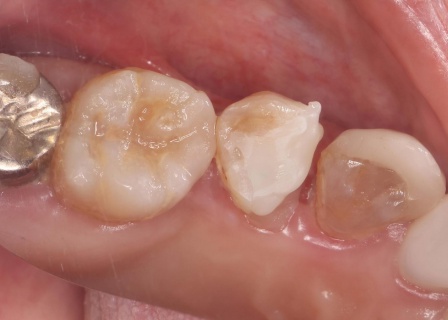

| 行ったご提案・治療内容 | 患者様は、歯をできるだけ残したいと希望されています。 そのため、感染した神経を取り除いて歯根内部を清掃・消毒する「根管治療」を行い、歯全体を覆う被せ物を装着する方法を提案し、同意いただきました。 メリット デメリット まず、根管治療で神経を慎重に取り除き、根管内の清掃と消毒を行います。 次に、歯を保護するための被せ物「ジルコニアクラウン」を装着します。 最後に、痛みや違和感がないか、問題なく噛むことができるかを確認し、治療を終了しています。 |

| 費用 | 約260,000円 (根管治療、ジルコニアクラウン) |

治療後